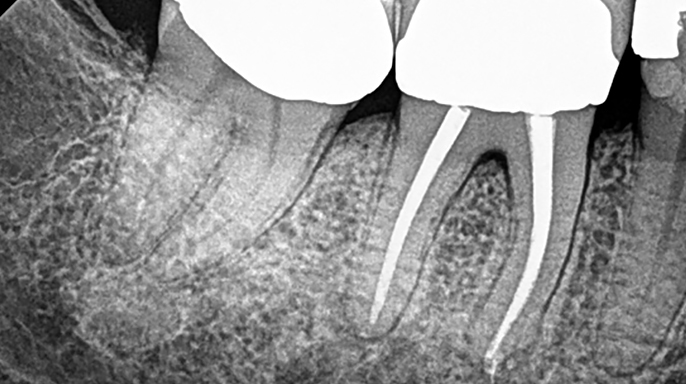

Úspěšnost nechirurgického ošetření kořenových kanálků je vysoká; nicméně nedostatečné zaplnění a utěsnění anatomických složitostí zásadně ovlivňuje dlouhodobý úspěch endodontické léčby.

Jako zubní lékaři často čelíme nutnosti revidovat ošetření kořenových kanálků kvůli problémům, jako je například netěsnost výplně nebo neadekvátní předchozí léčba. Náš imunitní systém naštěstí hraje zásadní roli při udržování křehké bakteriální rovnováhy bojem proti bakteriální agresi...